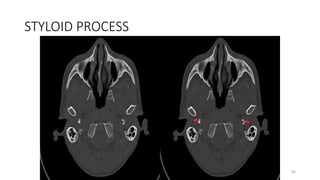

STYLOID PROCESS